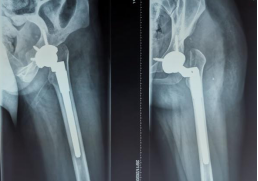

通过术前充分的准备,小张的手术也如约而至。当天在术中,毕郑刚和耿硕发现小张的患侧股骨头和髋臼都存在发育异常,没有软骨而且形状较不规则,难以契合,保髋方案不可取,于是只能采取方案二:全髋关节置换术。因为术前提前进行了规划,相应型号的假体也已经提前准备,髋臼假体及股骨假体安装得较为顺利。然而和预料的一样,在髋关节假体尝试复位时软组织张力较大,很难进行复位。因为在术前患侧股骨通过极限力量牵引验证了不截骨复位的可能性是存在的,为了能够让患者一期恢复腿长,避免二次手术,毕郑刚和耿硕决定通过进行软组织的松解来复位,选择了不进行股骨截骨,但是考验手术技术。经过对髋关节周围软组织的松解后,最终假体复位成功,随后通过比对双下肢长度,提示等长,关节活动度良好,宣告手术一期顺利完成。术后小张返回病房,因为未进行截骨仍有软组织张力大致神经血管等损伤的风险,术后嘱其行患肢适度屈髋屈膝位来减缓软组织张力,2~3周内逐渐伸直。术后通过查体,小张并未出现神经的损伤症状,手术成功。

(术后X线)